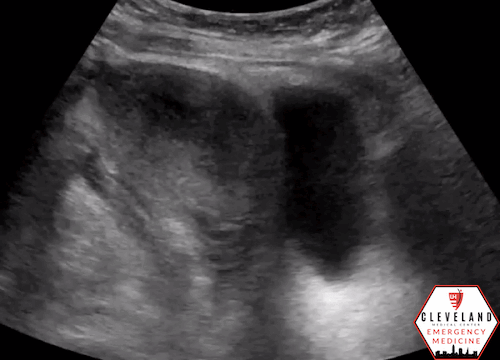

Renal POCUS was performed to evaluate for hydronephrosis and showed the following:

POCUS findings:

There is hydronephrosis of the left kidney. The right kidney is normal-appearing. Bladder views incidentally revealed a large complex, fluid-containing lesion in the pelvis (color doppler negative).